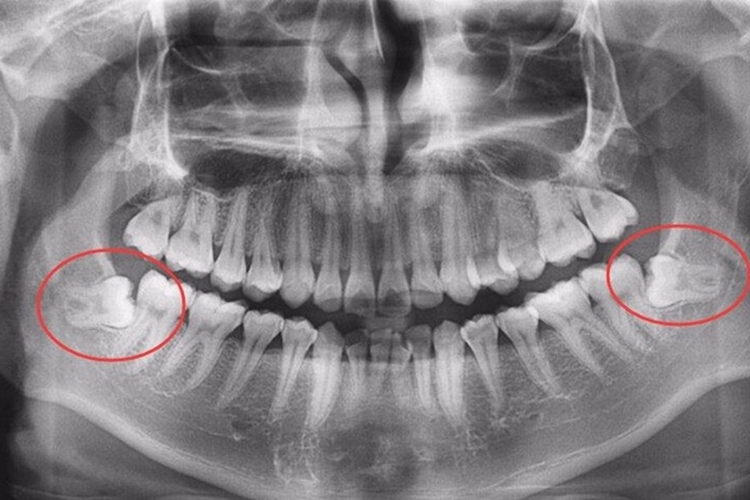

拔牙前准备:拔牙前往往需要拍片。拔牙时患者通常采用坐位或半坐位。医生会对患者口腔内手术区进行消毒、局部麻醉。

挺松患牙:对于阻生牙、坚固不易拔除的智齿,因不能用牙钳夹住,需应先用牙挺将牙挺松或用涡轮钻去骨、离断阻生齿后再拔除。